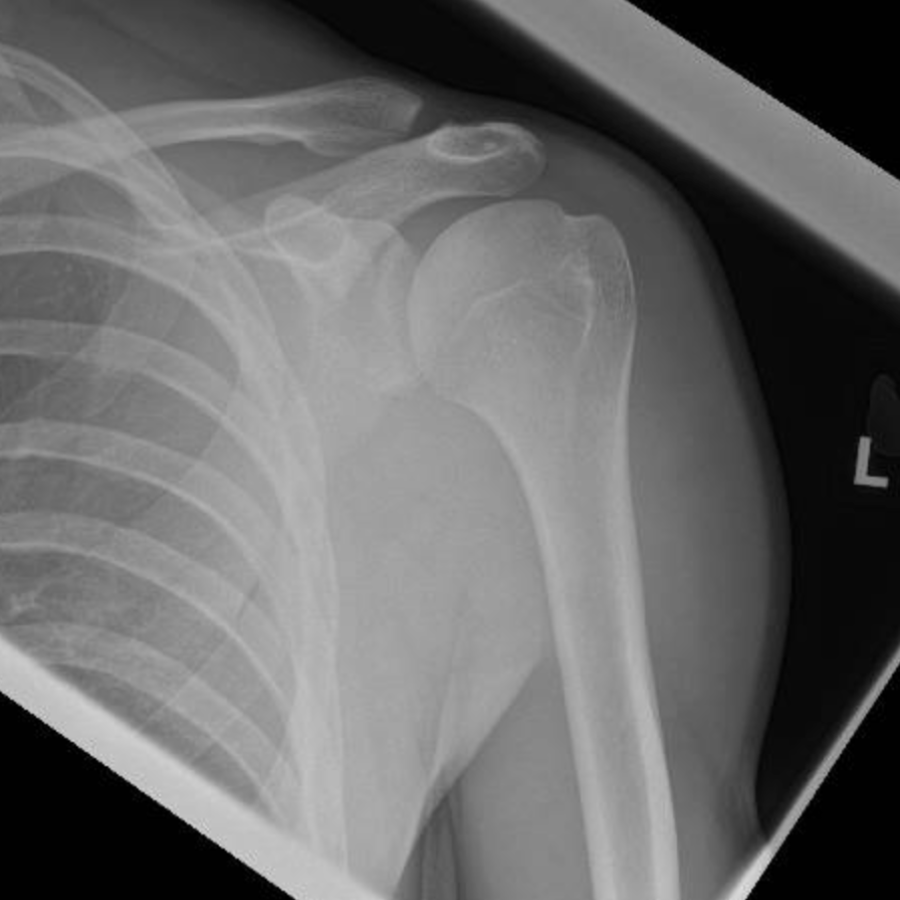

Arthritis of the shoulder is a condition where the smooth protective cartilage coverings on the ends of the bones making up the shoulder joint have worn away. Arthritis of the shoulder is less common than arthritis affecting the hip or knee. However the symptoms can be very disabling and can affect the function of the whole arm as well as causing severe pain.

Surgery is considered when other treatments are no longer effective in controlling your symptoms. Shoulder joint replacement is a very effective treatment for shoulder arthritis. The operation removes the arthritic joint surfaces and replaces them with a combination of metal and plastic surfaces. This operation is extremely successful in controlling pain and improving function of the shoulder and the whole arm. If you are being treated for shoulder arthritis and would like to find out more about shoulder replacements, or if your current treatments are not working, please book an appointment at The Cheshire Shoulder and Elbow Clinic.